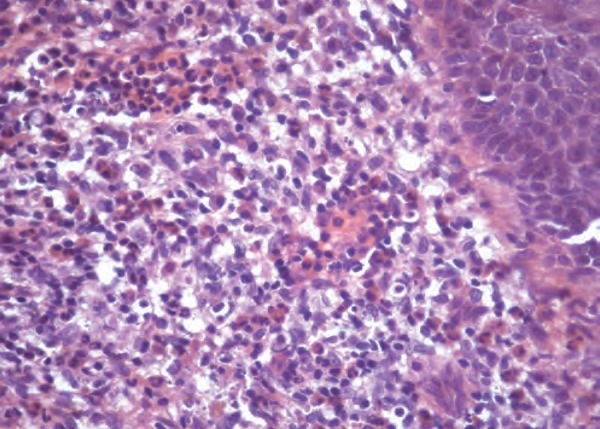

Диагностика лимфомы Ходжкина с помощью ПЭТ и КТ